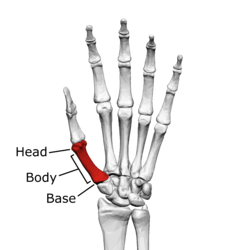

![]() The first metacarpal (Left) | |

Head

The head is less rounded and less spherical than those of the other metacarpals, making it better suited for a hinge-like articulation.

Body/Shaft

The body or shaft is thick and broad — averaging 6 to 11 millimetres (0.24 to 0.43 in). On its dorsal side, the shaft is flat and wide, while the anteroposterior side is less pronounced; usually resulting in an oval-triangular cross-section.

Base

The base is significantly different from the bases of the other metacarpals. It is trumpet-shaped and ends in a saddle-shaped articular surface matching that of the trapezial articular surface. The configuration of the thumb carpometacarpal joint plays an important role in the mechanism of opposition. The articular surface is delimited by a thick, crest-like ridge extending around its circumference.